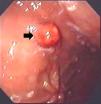

Presentación del casoMujer de 46 años de edad, de raza caucásica, quien presenta episodios transitorios de dispepsia de largo tiempo de evolución, sin pérdida de peso o cualquier otra sintomatología. Los exámenes de laboratorio reportan anemia hipocrómica. Fue referida a la Unidad de Endoscopia del Hospital de Clínicas, Brasil, donde se realizó una endoscopia digestiva alta, que reporta numerosos pólipos sésiles de 3 a 10mm, distribuidos en forma difusa en todo el fondo y cuerpo gástrico, algunos de los cuales están recubiertos por mucosa lisa y regular, y otros por mucosa rojiza.

También se encontró un pólipo pediculado de aproximadamente 40mm de diámetro (figs. 1 y 2), el cual fue removido mediante polipectomía con asa. El resultado anatomopatológico fue compatible con un pólipo hiperplásico con adenocarcinoma bien diferenciado, sin invasión vascular y con márgenes quirúrgicos libres de tumor (fig. 3).